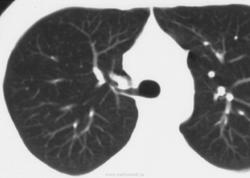

Бронхиальная атрезия.

Бронхоцеле

Бронхиальная атрезия

- в результате облитерации проксимального отдела сегментарного бронха (верхней доли), реже -долевой или субсегментарный бронх

• локальное вздутие пораженного сегмента

• бронхи дистальнее стеноза наполняются слизью - формируется бронхоцеле (мукоцеле)

• у новорожденных - вид кисты, заполненной жидкостью

• «воздушные ловушки» в результате гиперинфляции вокруг расширенных бронхов

• малочисленность сосудов в зоне поражения

• клинически - чаще бессимптомны

Бронхиальная атрезия.

Бронхиальная атрезия.

Бронхиальная атрезия.

Бронхиальная атрезия

Бронхоцеле

Атрезия бронха